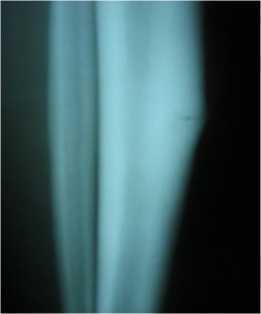

Рисунок 3 - Молодой спортсмен (19 лет). Прыжки в длину. Выраженная гиперпластическая реакция костной ткани

(перелом напряжения) в области дистального метадиафиза бедра.

Еще один случай перестройки костной ткани в большеберцовой кости.

Рисунок 4 - Молодой солдат С.Е. 1993г.р. Выраженная гиперпластическая реакция костной ткани (перелом напряжения)

в области проксимального метадиафиза большеберцовой кости.

Подростки-близнецы направлены на рентгенологическое исследование с жалобами на боль в верхней трети большеберцовой кости справа, связанные с большими физическими нагрузками, припухлость, нарушение функции правой нижней конечности. На рентгенограммах костей голени в верхней трети правой большеберцовой кости определяется деформация в виде утолщения кортикального слоя с признаками линии перелома (рисунок 4,5).